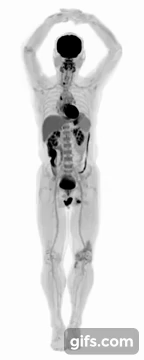

UC Davis scientists Simon Cherry and Ramsey Badawi have developed EXPLORER, a combined positron emission tomography (PET) and X-ray computed tomography (CT) scanner that can create 3D images of the entire body simultaneously.

The machine is made to capture radiation more efficiently than other scanners and can produce movies that can track specially tagged drugs as they move around the entire body. The scanner was developed in partnership with United Imaging Healthcare (UIH), based in Shanghai, who aims to eventually manufacture the devices for the broader healthcare market.

The first images from the scanner were shown at the Radiological Society of North America meeting last week. Badawi, Chief of Nuclear Medicine at UC Davis Health and Vice-Chair for research in the Department of Radiology explained:

“The level of detail was astonishing, especially once we got the reconstruction method a bit more optimized. We could see features that you just don’t see on regular PET scans. And the dynamic sequence showing the radiotracer moving around the body in three dimensions over time was, frankly, mind-blowing. There is no other device that can obtain data like this in humans, so this is truly novel.”

The researchers are currently using the EXPLORER to in medical studies to demonstrate how it can benefit patients and contribute to inform others of the whole human body in health and disease.